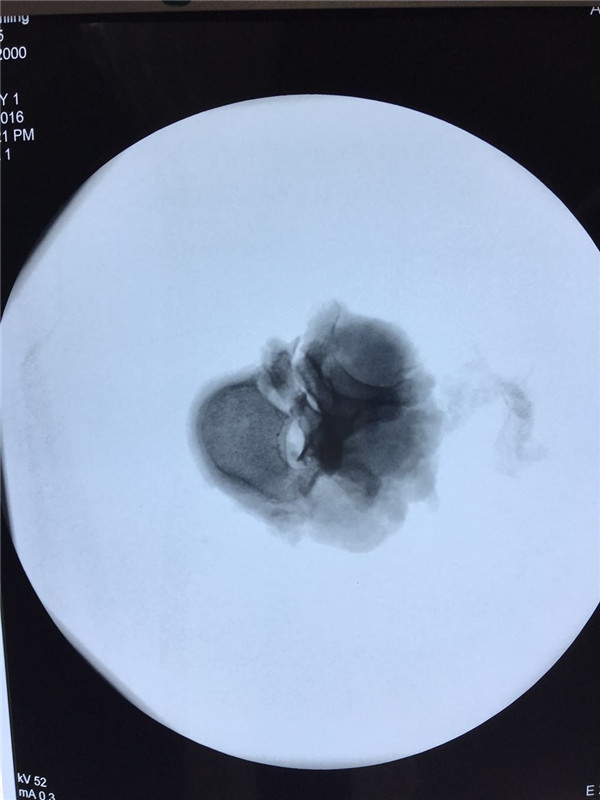

术中透视